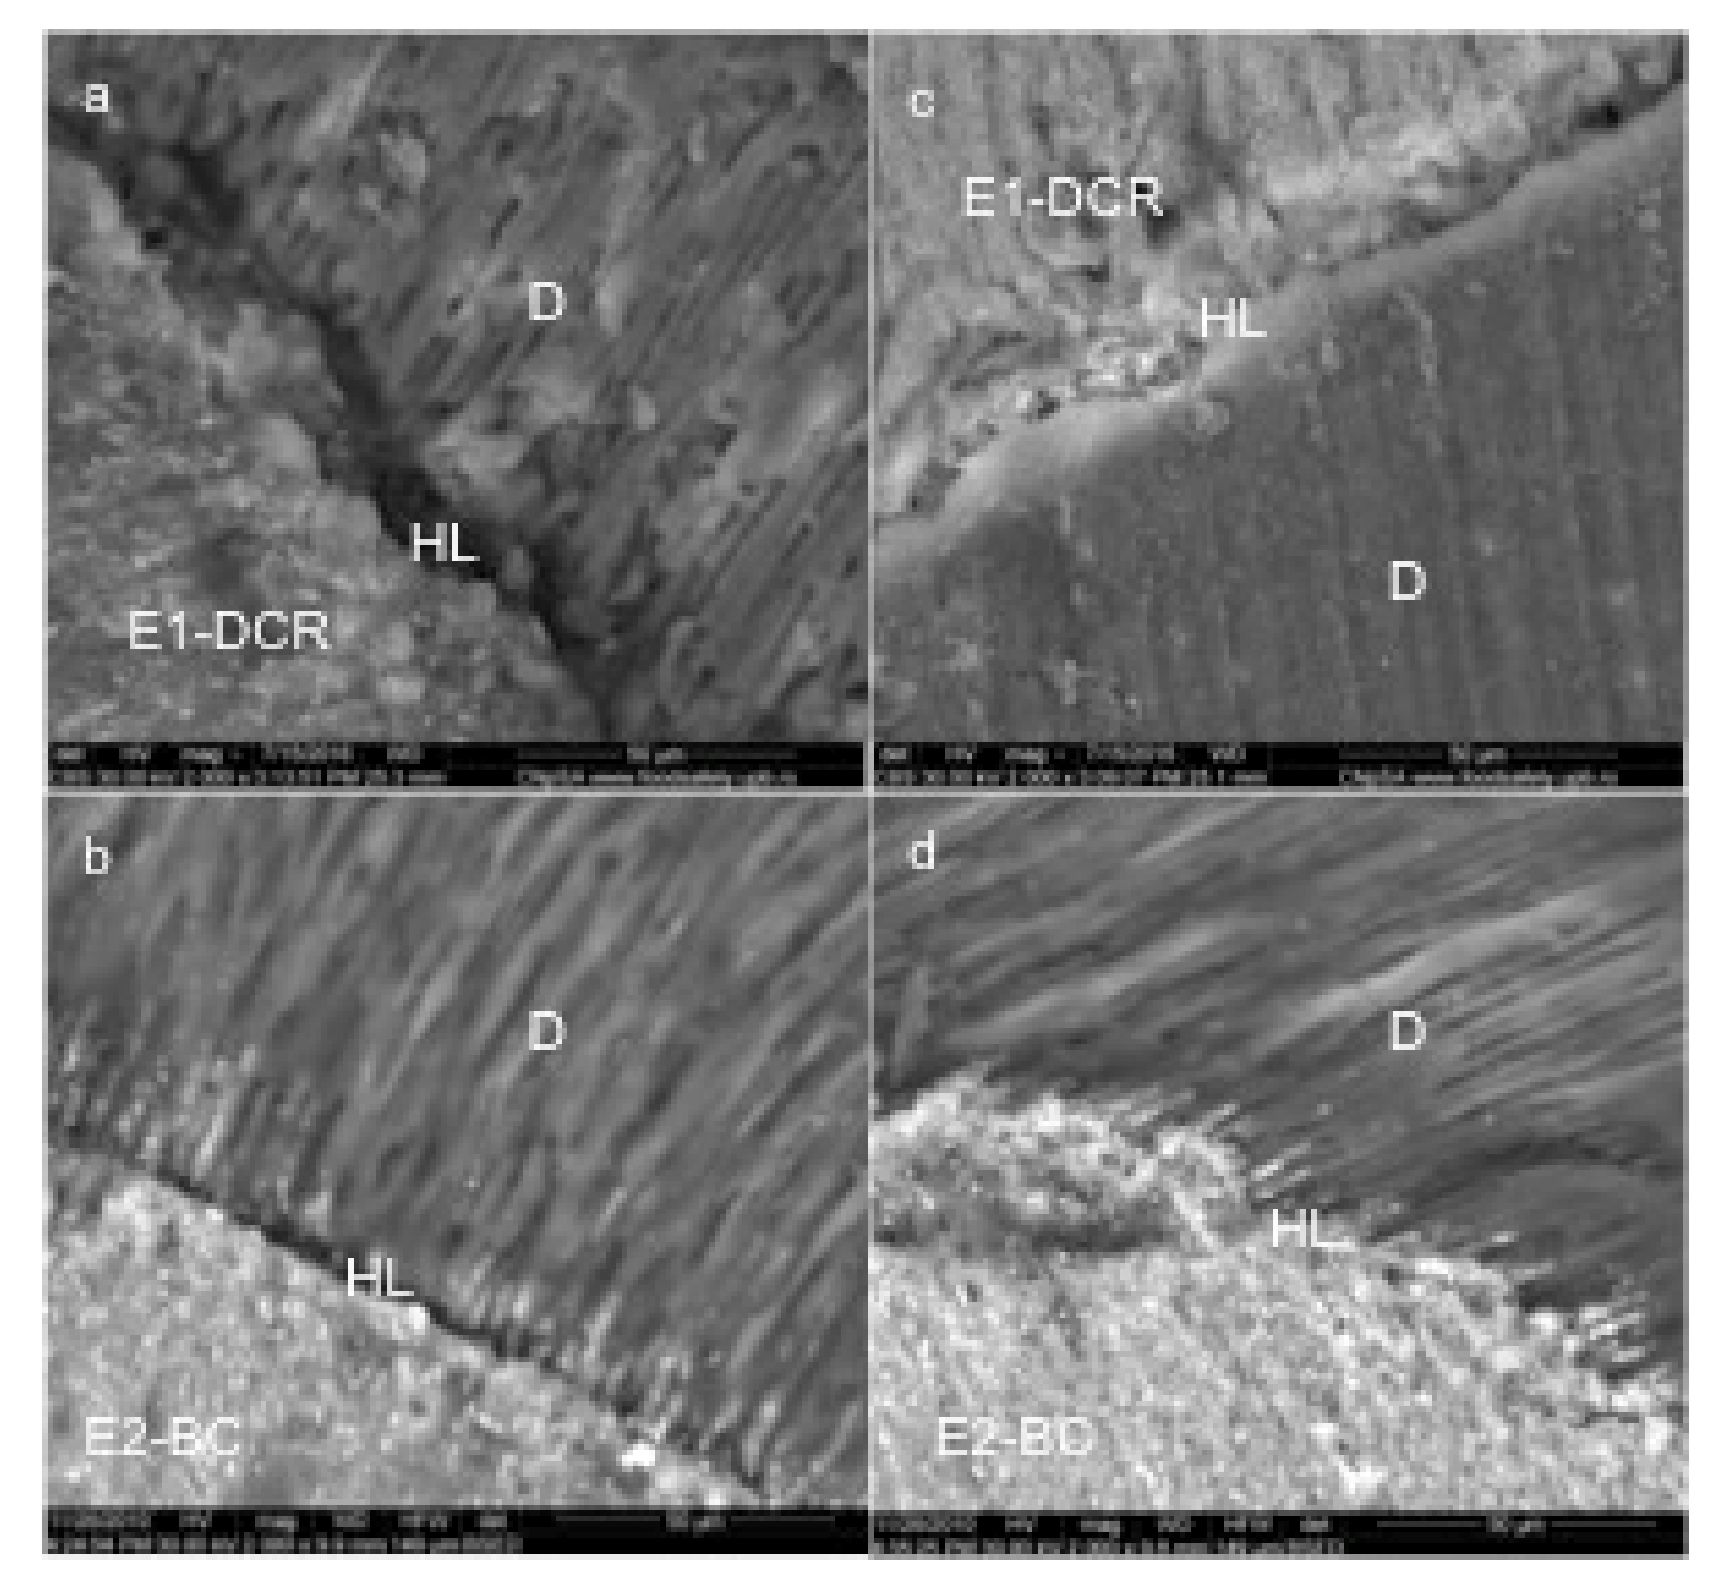

Representative SEM images of experimental sealers (magnification 2000X): dual cure resin experimental sealer E1-DCR (a,c); bioceramic experimental sealer E2-BC(b,d); HL-hybrid layer, D-dentin.

A high degree of homogeneity was also identified for the polymerized experimental E2-BC sealing material. The E2-BC sealant extensions that intersect the hybrid layer have a similar electron density with the overlying layer, which demonstrated a continuity of the concentration of bioceramic nanoparticles to depth. The periphery of the dentinal canals was “hybridized” and the hybrid layer obtained with this material extends over the entire depth of the demineralized area. In other words, the sealer mediated a complete adaptation between the dental structures and the gutta-percha (Figure 2b).

The E1-DCR sealant did not penetrate deep into the dentinal canals; SEM analysis showed that the non-adherent dentinal surfaces still had sealant residues and most of the orifices of the dentinal tubules were clogged, thus creating the conditions for mechanical retention and a satisfactory seal (Figure 2c).

The E1-DCR material does not present a significantly improved apical sealing ability when compared to the E2-BC material (Figure 2d).

The evaluation of the experimental materials using SEM has shown a homogenous layer on the apical region, with extensions intersecting the hybrid layer.